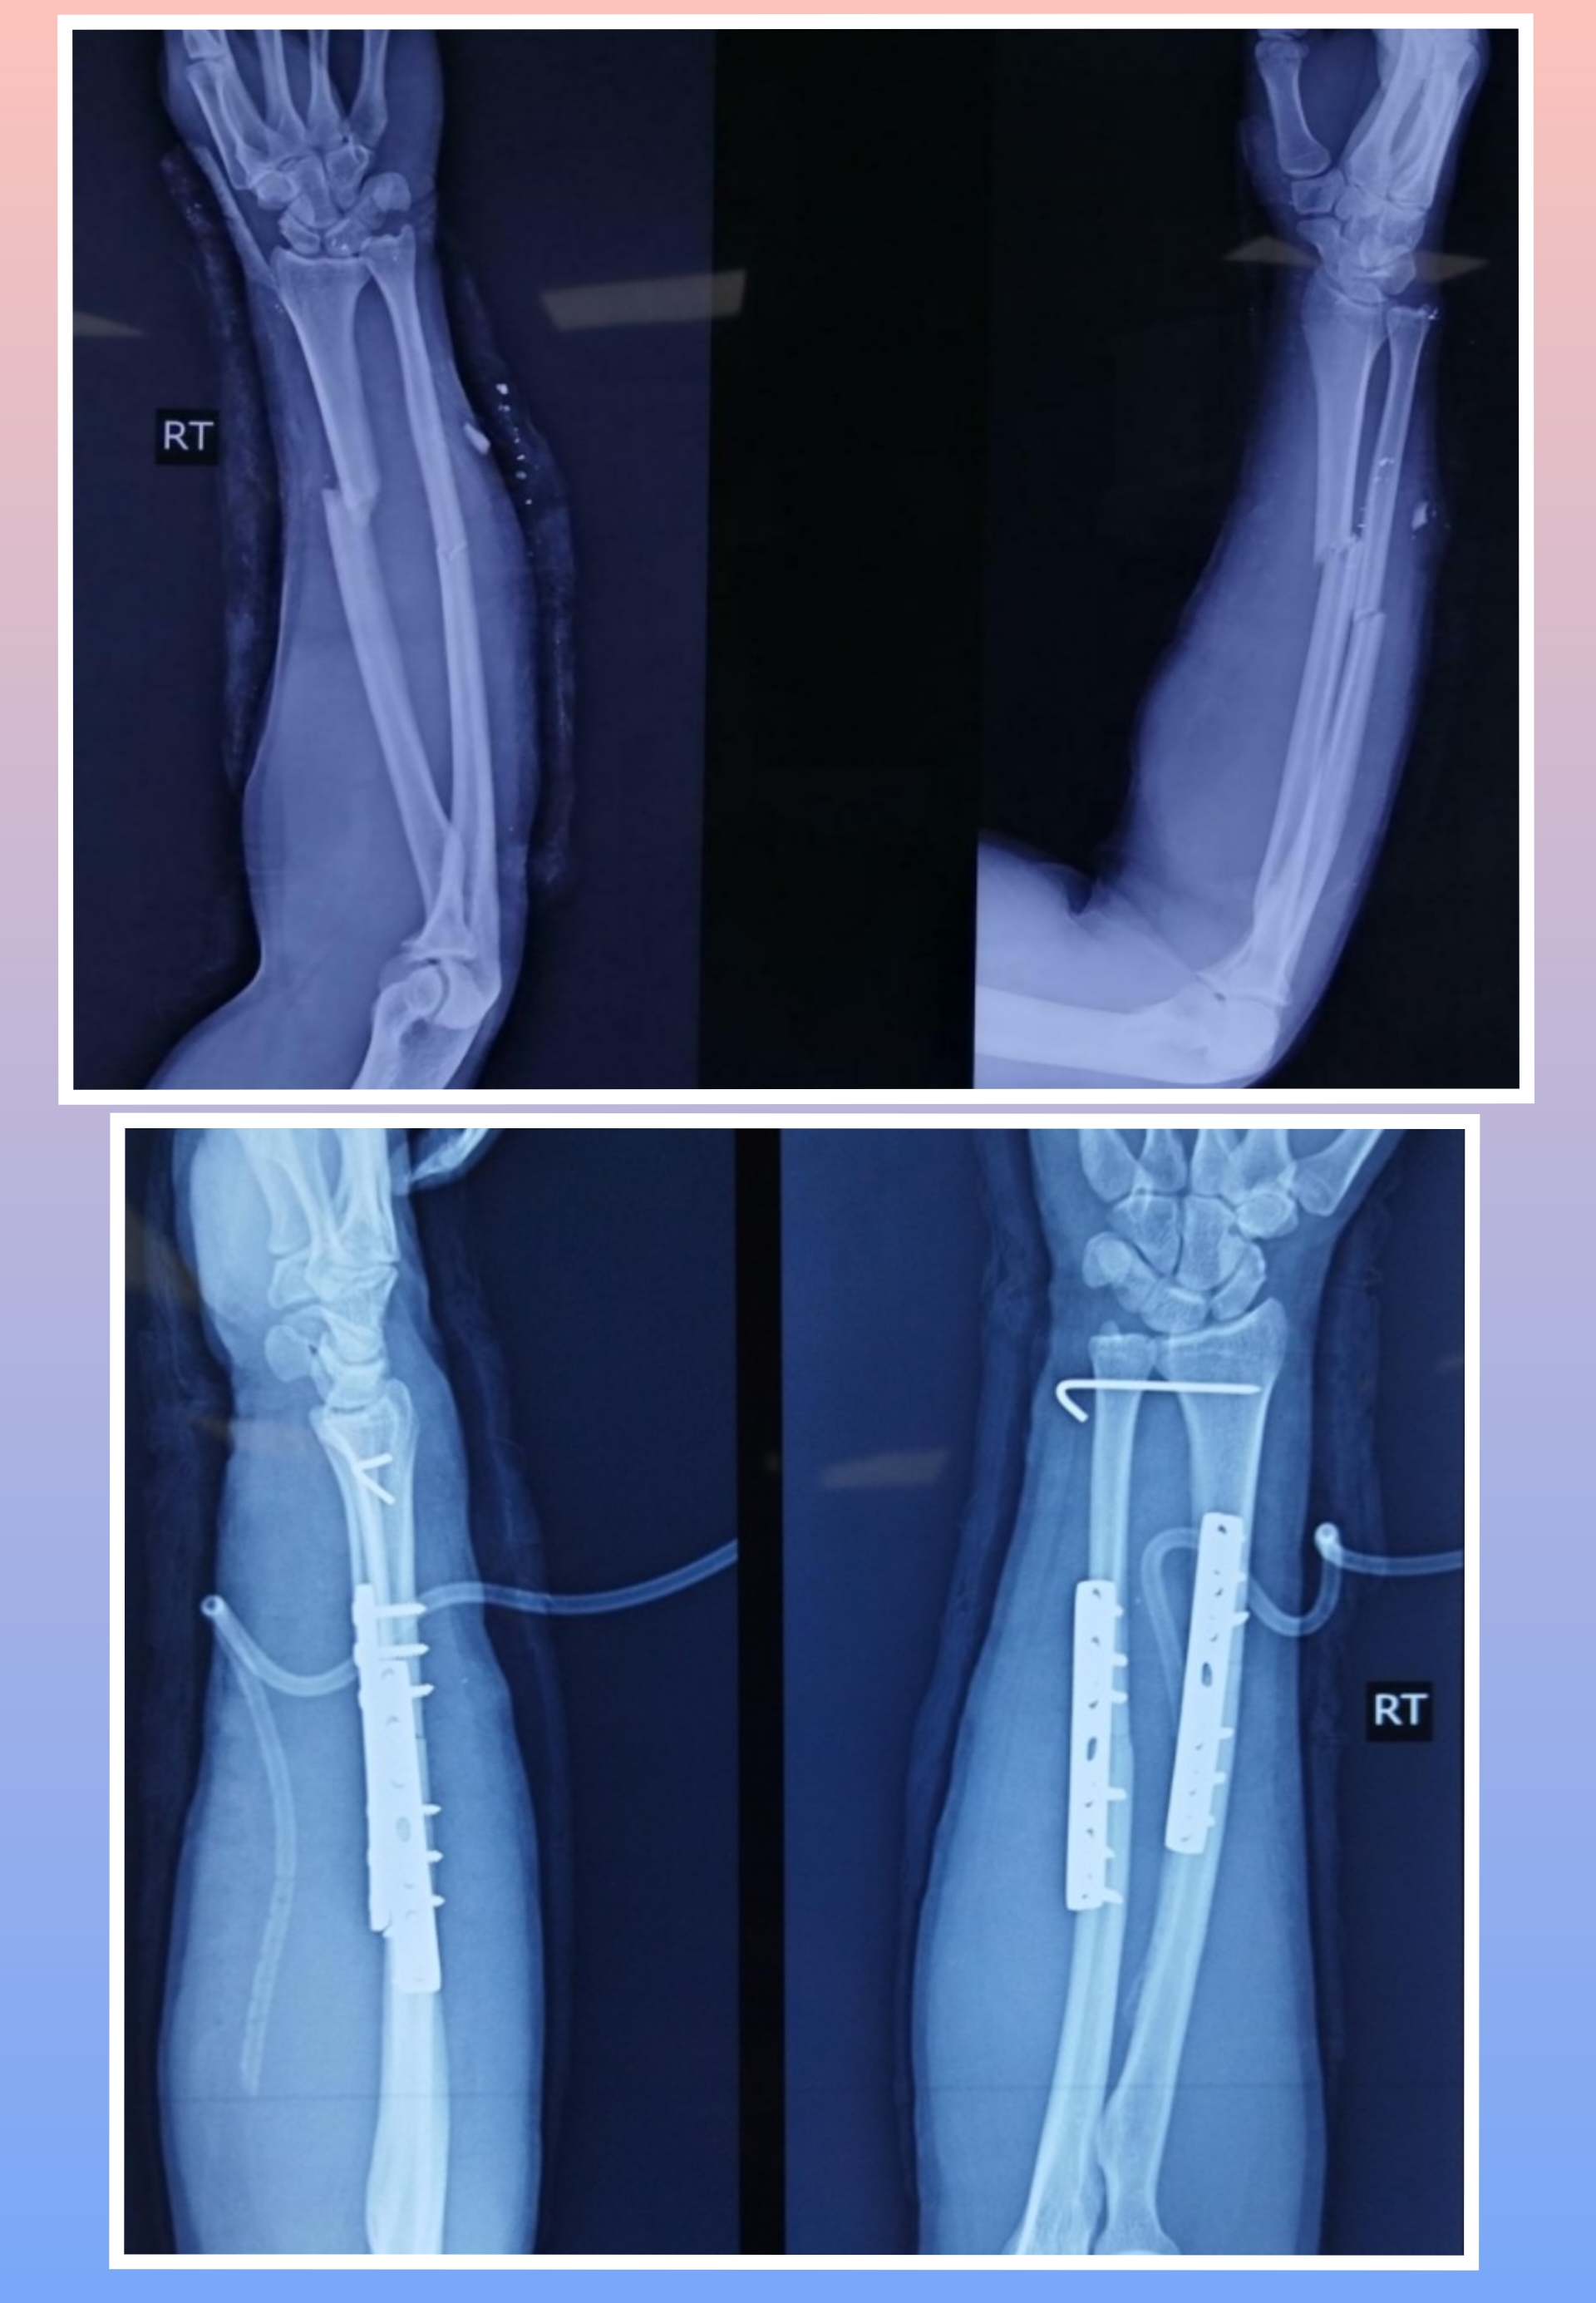

X-ray

Surgeries